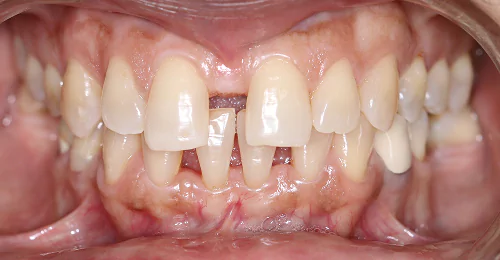

Anterior Crossbite Correction

Without Extraction Of Teeth

A young newly married female had crossbite in front teeth and when she smiled she felt her teeth appeared crooked. Being newly married she also had concerns regarding wearing braces. Assessing the situation, we advised ceramic braces and treated the condition without extracting or removing any teeth.

Pre Treatment

The treatment was completed successfully after a period of 18 months. Our patient is now embarked on her newly married life with more confidence.